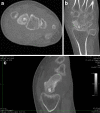

Osteoid osteoma of the scaphoid presenting with radiocarpal arthritis: a case report

A case of osteoid osteoma of the scaphoid presenting as painful monoarticular arthritis is presented. Degenerative arthritis, associated with osteoid osteoma of the carpus, has not been described. The implications for treatment are discussed.